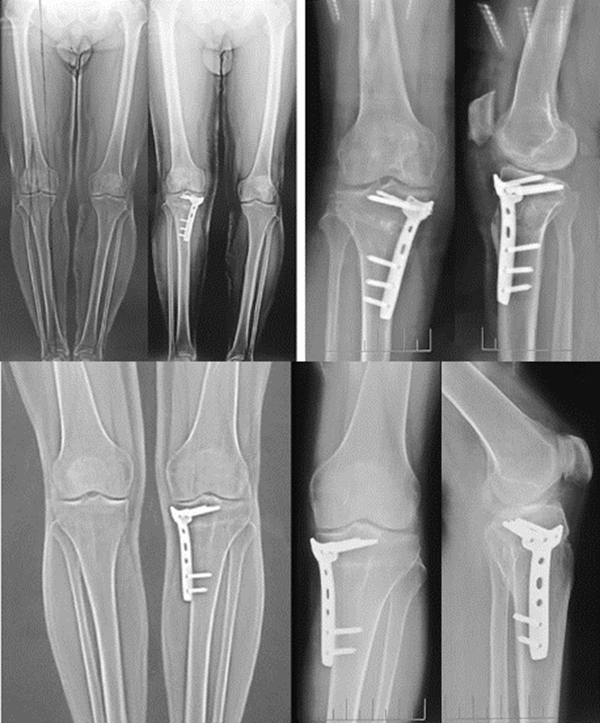

病例1:46岁,滑雪运动员,多发韧带伤,内翻畸形膝关节疼痛,开式截骨后二月全负重行走,膝关节疼痛缓解

病例2:男性,19岁,因发现右膝关节内翻、过伸畸形伴跛行5年(左侧膝关节也有类似畸形,暂时无症状)。于2006年7月就诊,其母亲也有类似病史。查体:右膝关节内翻畸形约15度,应力下过伸约20度,内翻及外翻时膝关节均有松动感,Lanchman试验(+)。无负重下X片示:右膝关节内翻畸形约15度,胫骨平台无后倾,倒呈前倾13º。膝关节MR示:右膝内侧股骨及胫骨软骨面已有缺损并囊性变。诊断:先天性膝关节内翻畸形(Blount病)。

术前X线可见右膝关节内翻畸形约15°,胫骨平台前倾畸形13°

术前膝关节MR示:右膝内侧胫、股骨骨软骨面已有缺损并囊性变

应力位过伸畸形明显

术后6月X片示右膝内翻、前倾畸形已矫正,胫骨截骨处愈合,腓骨未愈合,但无症状。